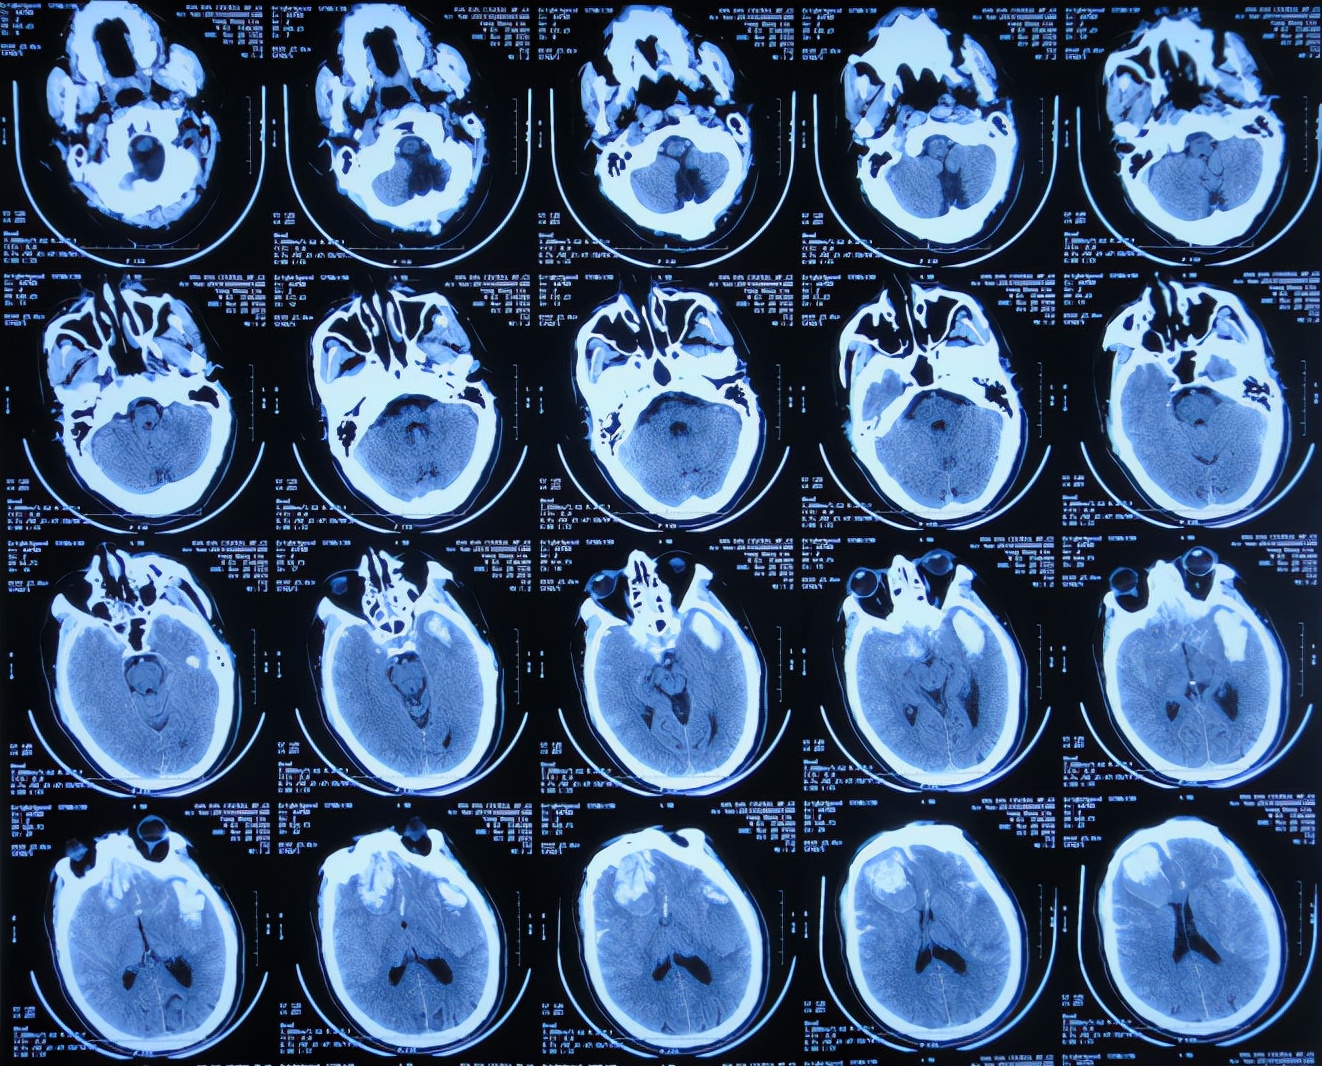

2019年10月20日患者骑电动车在马路上行驶时被大货车撞倒,当时意识清楚,只感到有些头晕,未在意就自行回家,但回家后约3-4小时出现头晕加重,并伴有恶心呕吐的症状,家人急送到当地的河北省邯郸市某医院,查头颅CT示脑出血( 图-1 );既往病史2015年曾因头部外伤致硬膜下血肿,进行了钻孔引流术。

图-1: 2019年10月20日头颅CT